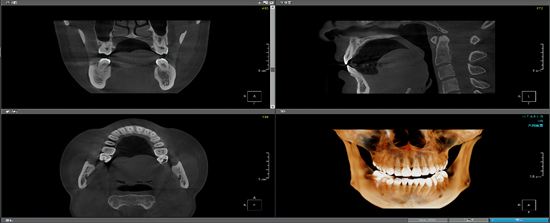

工作室团队成员目前包括李思博士、何远清老师、胡晨恺医生(南昌大学第二附属医院心内科主治医师)。另现有7名员工成员,包括20级1名、21级1名、22级5名,员工成员目前的研究主题包括:基于深度学习的冠脉造影狭窄智能检测技术研究(如图1所示);基于神经网络的智慧城市停车位检测技术研究(如图2所示);基于深度学习的口腔CT牙槽骨分割技术研究等(如图3所示)。

图3:基于深度学习的口腔CT牙槽骨分割技术研究